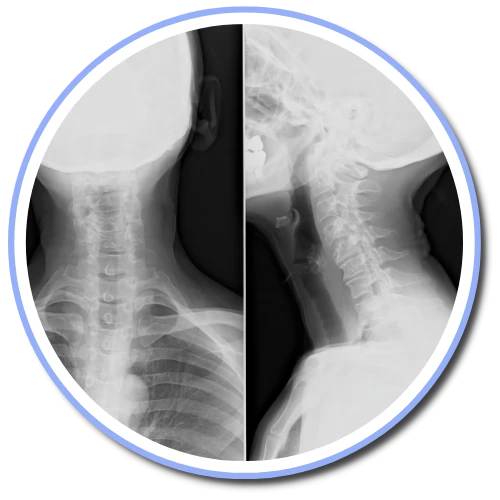

Incledon Chiropractic Center uses the Gonstead method of adjusting and analyzing the spine. We're one of a few offices in Fishkill that exclusively uses the Gonstead method. By thoroughly analyzing the spine through the use of x-ray, instrumentation, visualization, static and motion palpation you can expect a properly delivered adjustment.